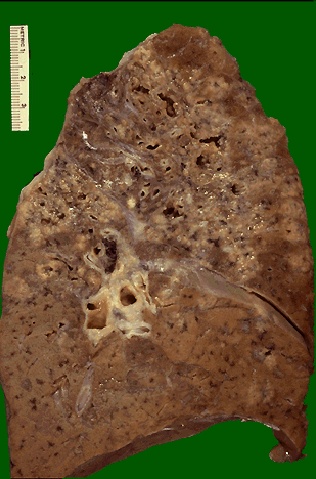

| When there is extensive caseation and the granulomas involve a larger bronchus, it is possible for much of the soft, necrotic center to drain out and leave behind a cavity. Cavitation is typical for large granulomas with tuberculosis. Cavitation is more common in the upper lobes. |